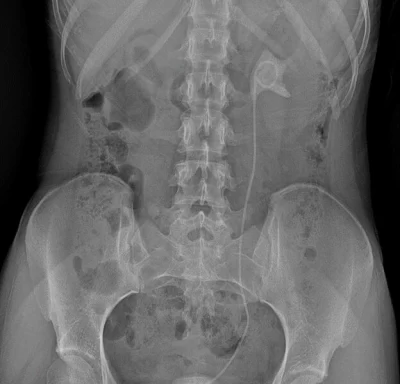

Ярославские врачи помогли девушке, забывшей удалить стент из мочевого пузыря

Современные технологии и опытные специалисты вернули здоровье 18‑летней пациентке. Непростой, но успешный курс лечения юной больной завершился во втором уро...